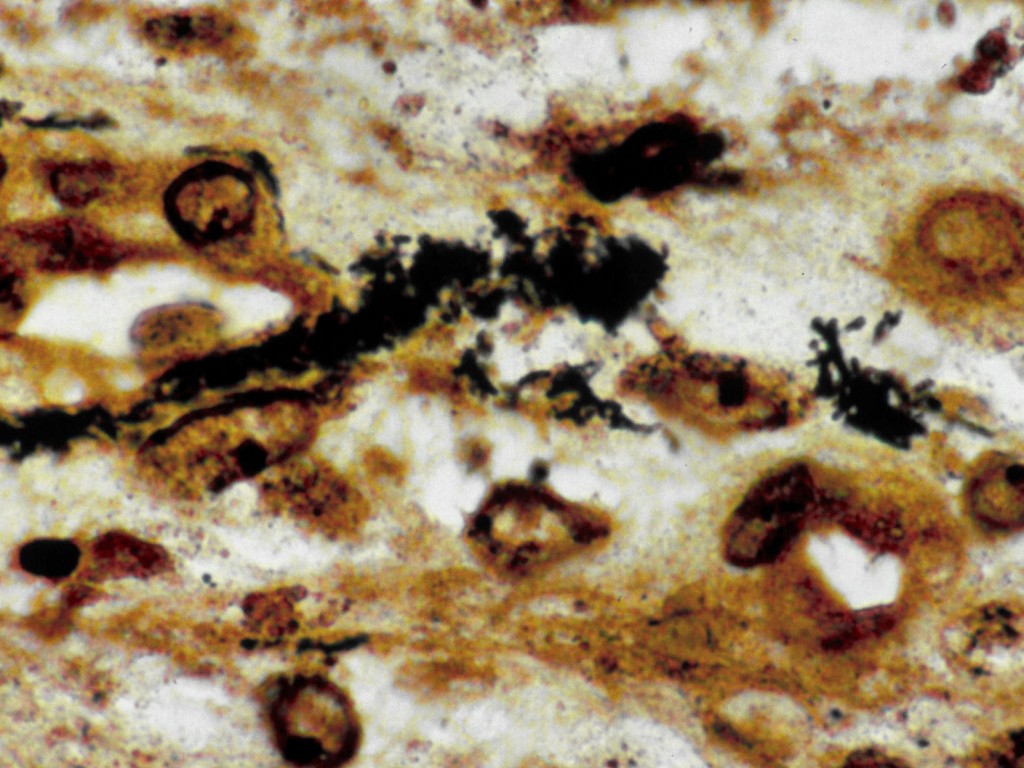

Whartin-Starry

kleuring |